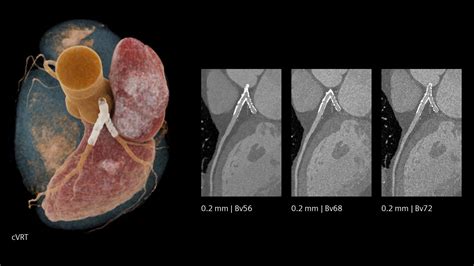

When it comes to diagnosing heart conditions, precision is paramount. A Cardiac CT, also known as a coronary computed tomography angiography (CCTA), has revolutionized the way medical professionals visualize the complex structures of the heart. By utilizing advanced X-ray technology coupled with powerful computers, this non-invasive diagnostic tool creates detailed, three-dimensional images of your heart, its arteries, and the surrounding tissues. Whether you are experiencing unexplained chest pain or have known risk factors for cardiovascular disease, understanding how this procedure works can help alleviate anxiety and prepare you for your medical journey.

At its core, a Cardiac CT scan is an imaging test that allows cardiologists and radiologists to see if your coronary arteries are narrowed or blocked by plaque buildup—a condition known as atherosclerosis. Unlike traditional stress tests, which provide functional information about how your heart handles exertion, a cardiac CT provides anatomical information. It captures images of the heart while it is beating, using sophisticated gating technology to synchronize the image acquisition with your heart rhythm.

This technology is particularly effective at identifying early-stage heart disease before symptoms manifest. By visualizing the calcified and non-calcified plaque within the arterial walls, physicians can initiate preventative treatments far earlier than previously possible.

Once the scan is complete, the images are sent to a radiologist or a specialized cardiologist who analyzes the anatomy of your coronary arteries. They will look for the presence and extent of plaque, the degree of arterial narrowing (stenosis), and the presence of any calcium deposits. You will receive a formal report, and your primary doctor will discuss the findings with you to determine the next steps in your care plan. Depending on the findings, these steps may include lifestyle modifications, cholesterol-lowering medication, or further diagnostic testing.